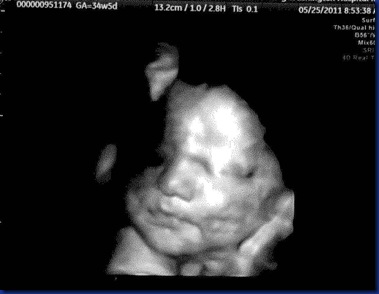

Today we got to check in on Maisy and see how the baby girl is doing.  She’s growing!  A lot!  She now weighs 6 pounds 4 ounces!  Her abdomen was measuring ahead of schedule, but hopefully that’s stemming from nothing more than her being a big baby.  I begged asked nicely for a new picture, and the sweet sonogram tech tried really hard to get me one, which resulted in me laying on my side with her jamming the wand into my hip bone aiming down to try to get a good angle of her face.  It’s really hard at this point because she’s so low and so squished in there!  But here is what we got (sorry it’s kinda creepy how there is a reflection of her face, I promise she doesn’t have 2 heads!)

Maisy34weeksB

Maisy34weeksA

Look at those cheeks!!!!! :) She is so sweet already! I can't wait to meet her! I hope that they call you this week with some good news about the other doctor.. fingers crossed!!!!!!!! Everything will work out though, try not to stress too bad!

Oh and the tech did a fantastic job on getting that perfect shot of Maisy. She has the sweetest chubbiest face, ahh can't wait to see her in person!!!